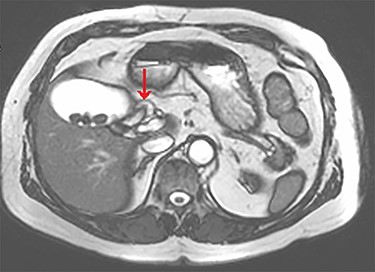

The tubular structure was remote from the porta hepatis with one lumen. It was located within the distal gallbladder fossa. Inspection of the gallbladder demonstrated an opening at the same orientation and of the same calibre as this tubular structure, raising suspicion for a duplicated cystic duct. Probing the source of the bile leak confirmed a single lumen. The capacity to perform IOC was not available at the time of the operation. A review of the patient’s prior imaging was performed. Recent cardiac magnetic resonance imaging (MRI), while not dedicated magnetic resonance cholangiopancreatography (MRCP), provided adequate views of the liver, gallbladder and biliary tree to demonstrate the suspected anomaly. On these images, two structures were seen to be connecting the gallbladder to the biliary tree. One duct was observed at Hartmann’s pouch, while a second connected to the gallbladder body (Fig. 1, Fig. 2). The images confirmed suspicion of a duplicated cystic duct and the decision was made to clip the lumen. The cholecystectomy was completed and a drain placed in the gallbladder fossa.

Axial view of the liver and gallbladder from a cardiac MRI showing the normal location of the cystic duct entering Hartmann’s pouch (highlighted by the arrow), which is separate and distinct from the structure shown in figure 1.